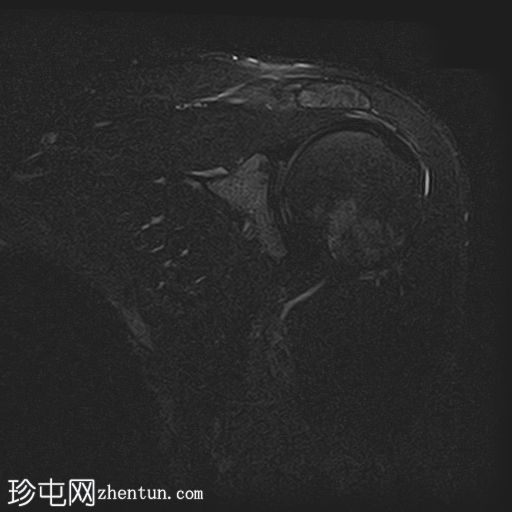

8.jpg

轴位PD加权像

脂肪抑制像

冈上肌腱上部纤维可见约25 x 1.2 mm的低信号肌腱内病变,符合钙化性肌腱炎的影像学表现

冈上肌腱滑囊侧纤维可见液体信号增高,符合肌腱病

II型肩峰(弯曲型)

肩峰下滑囊内可见轻度液体信号,提示轻度滑囊炎